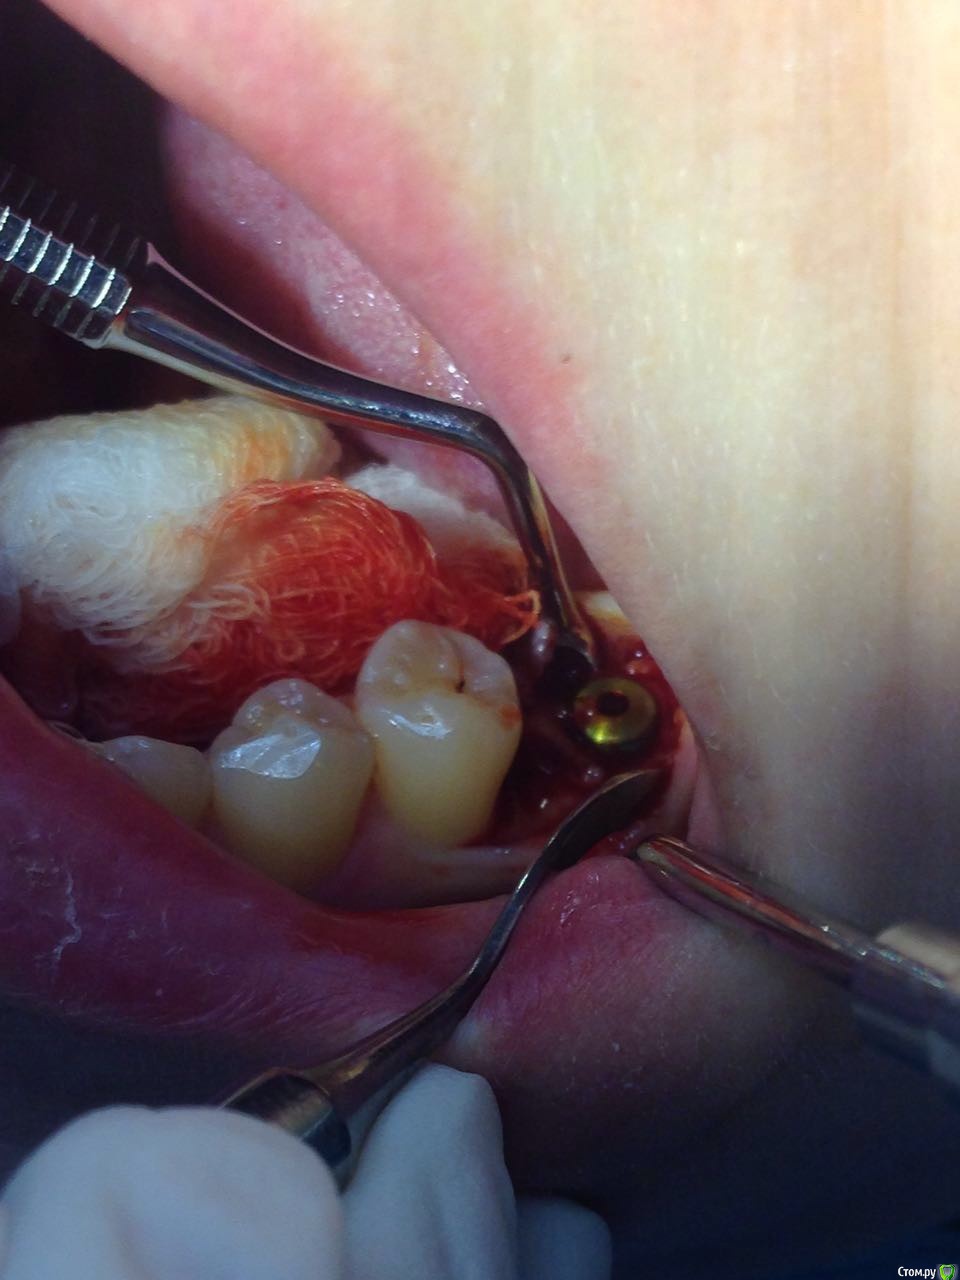

Madira Опубликовано 16 марта, 2016 Автор Поделиться Опубликовано 16 марта, 2016 Врач сегодня сфотографировала 2 нижних импланта. Что-то по этим фотографиям можно сказать? Насколько криичная ситуация? Ссылка на комментарий

diesel87 Опубликовано 16 марта, 2016 Поделиться Опубликовано 16 марта, 2016 То же что и по снимку, резорбция кости по шейке имплантатов. И так же, судя по нему, скорее всего нижние 2 импланта не были установлены вровень с костью, скорее всего на 0,5-1,0 мм над уровнем кости. С установкой фдм возможно картина станет лучше, отдохните пока, погуляйте 3-4 недели с ними, мягкие ткани должны успокоиться. Ссылка на комментарий

Madira Опубликовано 16 марта, 2016 Автор Поделиться Опубликовано 16 марта, 2016 (изменено) Спасибо. Врач сказала, что резорбция произошла не со всех сторон импланта. Это на последних фото как-то видно? Или видно четко, что он именно не докручен со всех сторон одинаково? 3 недели с удовольствием отдохну)))Мне моя врач тоже самое и посоветовала)) Но что дальше? Жить с ними не надеясь на их долговечность? Изменено 16 марта, 2016 пользователем Madira Ссылка на комментарий